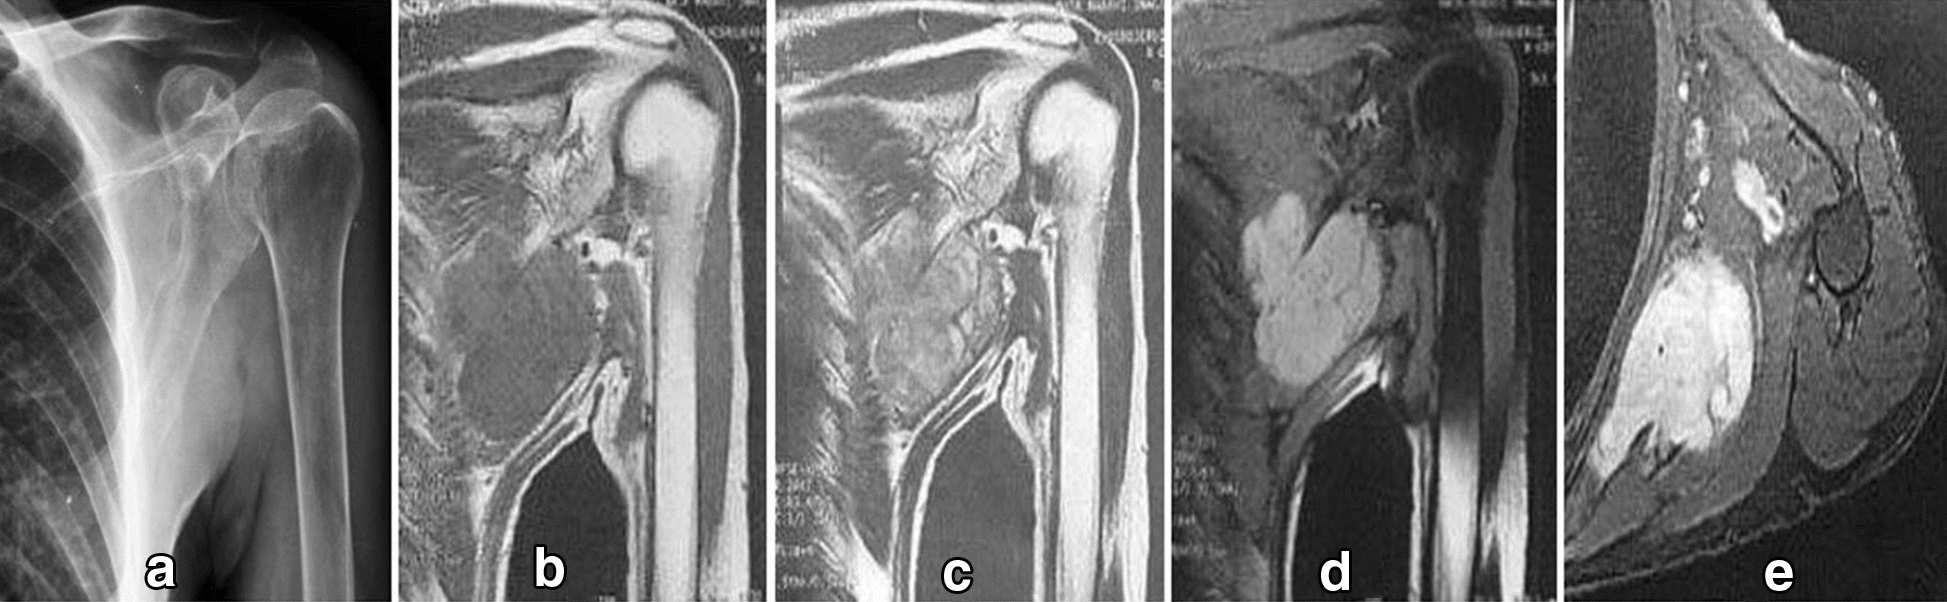

The chest X-ray and shoulder X-ray of our patient were insignificant. His left shoulder magnetic resonance imaging (MRI) revealed a 5-cm (in the largest diameter) left axillary soft tissue mass at the mid-axillary line. The tumor was deep to the fascia and over the posterolateral chest wall extending from third to fifth ribs with no visible rib cage involvement [Fig. 1].

Fig. 1.

Diagnostic imaging. a Radiograph shows a soft tissue lesion affecting chest wall in the infra-axillary region. b–e, MRI shows a lobulated mass iso-signal in T1W and heterogeneous to high signal in T2W and high signal in fat-saturated sequences with strong post-contrast enhancement in the infra-axillary intermuscular fat plane. The tumor had close contact with adjacent vessels